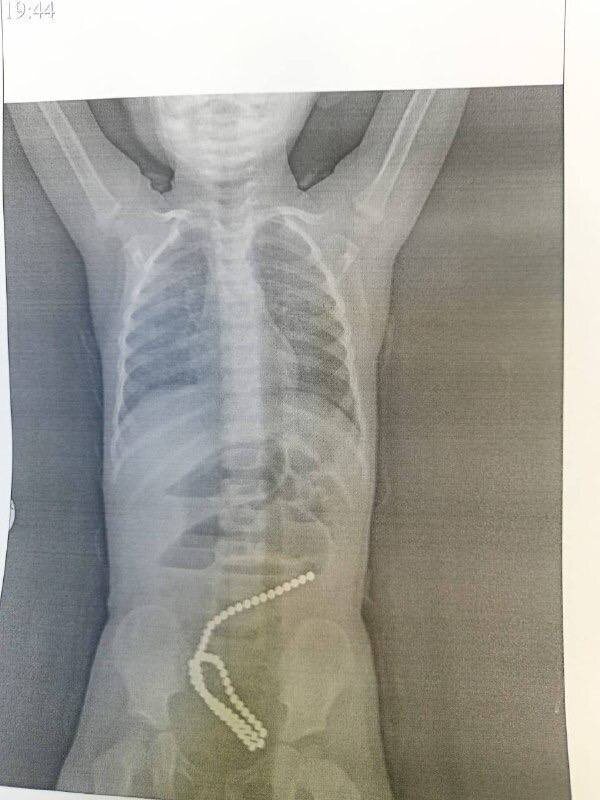

Двухлетняя девочка в Комсомольске-на-Амуре проглотила 60 маленьких магнитов-шариков Родители забили тревогу, когда ребенок начал жаловаться на сильную боль в животе. При обследовании у девочки обнаружили магниты. Они вызвали кишечную непроходимость, повреждение стенок кишечника. Хирурги успешно провели сложную операцию, которая длилась почти два часа. Спустя две недели девочку выписали домой.

Родители забили тревогу, когда ребенок начал жаловаться на сильную боль в животе. При обследовании у девочки обнаружили магниты. Они вызвали кишечную непроходимость, повреждение стенок кишечника.

Хирурги успешно провели сложную операцию, которая длилась почти два часа. Спустя две недели девочку выписали домой.